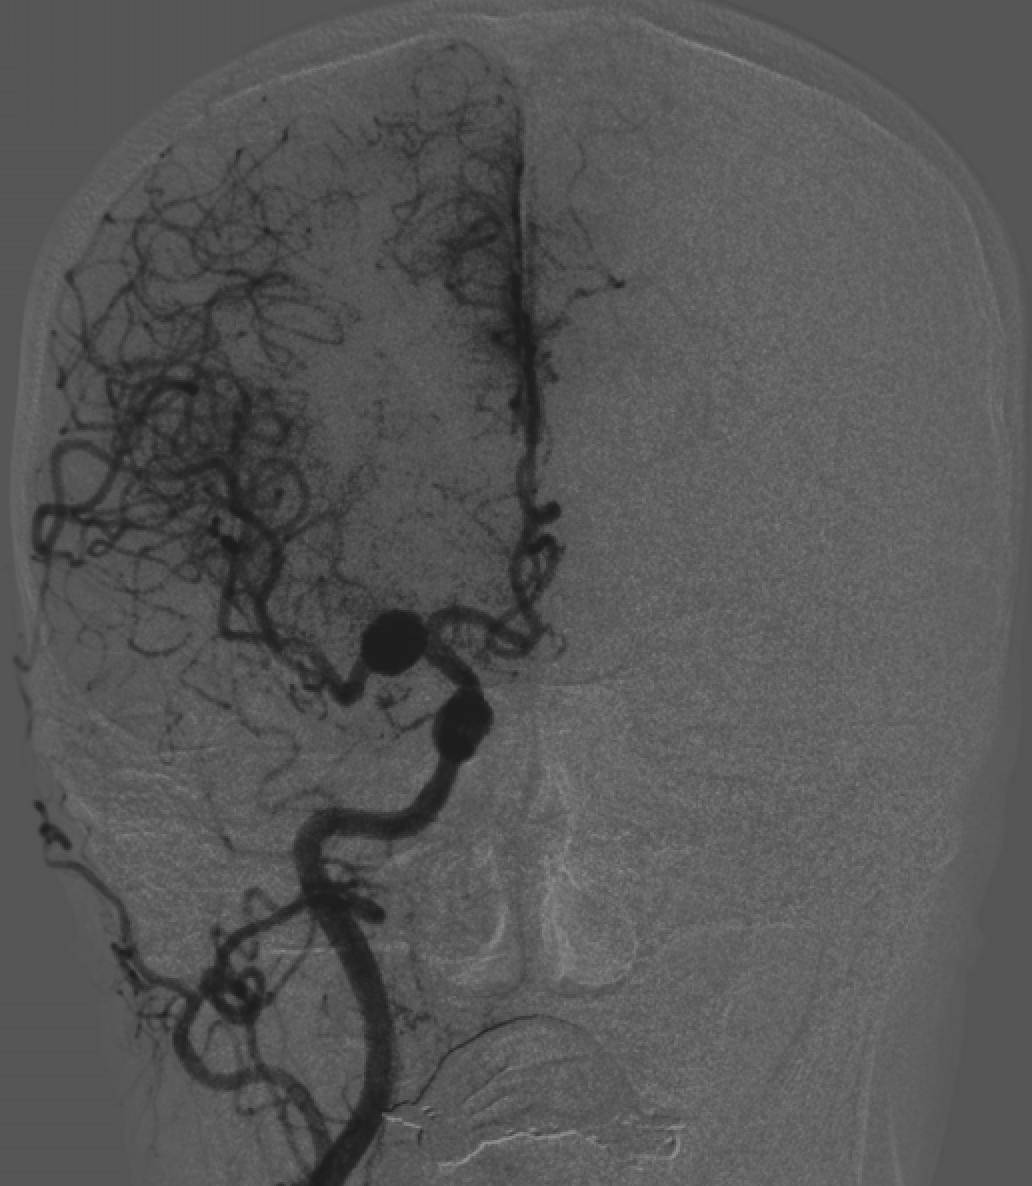

术前正位DSA

初步诊断:左侧大脑中动脉M1段动脉瘤

侧别、位置:左侧

动脉瘤的形态:囊性

动脉瘤大小:长24.8mm、宽23.1mm、高20mm

动脉瘤颈宽度:6.2mm

载瘤动脉直径:远端3.1mm,近端3.9mm

动脉瘤特征:M1段动脉瘤体积巨大,瘤颈宽大,瘤腔容积大,单纯弹簧圈难以实现致密栓塞,复发风险高。

解剖位置:瘤颈邻近分叉及穿支动脉,M1段血管长度有限,操作空间狭窄,要求支架定位精准且不影响分支灌注。

血管径差:远近端管径不一致,常规FD容易出现贴壁不良或位置不稳。